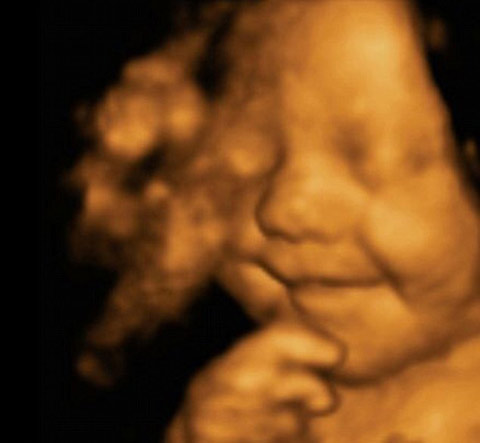

Grinning from ear to ear, this picture shows little Leo Hargreaves was rather happy with his world – even before he was born.

The remarkable image was taken from an ultrasound scan at 31 weeks.

The image is a 4D scan - increasingly popular with expectant parents to get a glimpse of how their child will look.

Rather then the grainy ‘flat’ images produced by the 2D scanners usually used by the NHS, a 4D machine stitches together pictures taken from a variety of angles to create clear three-dimensional images.

These are then recorded on video – the fourth dimension.

照片上這位名叫里奧?哈格里夫斯(Leo Hargreaves)的小寶貝還未出生就已經(jīng)咧著嘴笑個不停,一臉幸福的樣子。

這張與眾不同的照片來自于超聲波掃描,當(dāng)時里奧才31周大。

圖像由4D掃描采集。這項技術(shù)越來越受準(zhǔn)爸爸準(zhǔn)媽媽的歡迎,他們迫不及待地想要一窺自家孩子的模樣。

英國國民保健服務(wù)(NHS)通常使用2D掃描,由此拍出的圖像是平面點狀物,而4D掃描則將多角度拍攝而成的圖片拼接在一起組成清晰的三維圖像。

這第四個維度就是寶寶在母親肚子里的一舉一動被記錄成像。